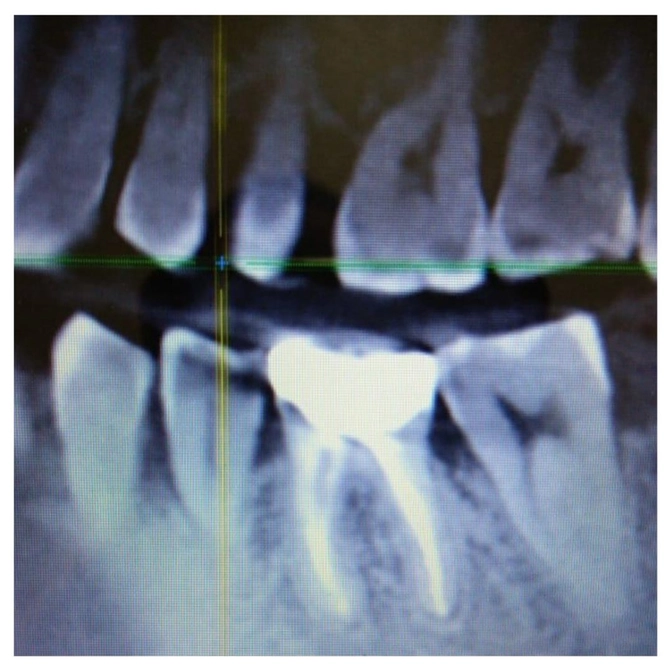

А на рентгене сразу видим - КИСТА.

Киста - это патологическая полость с плотными стенками, заполненная жидкостью из погибших клеток, бактерий и т.п.

Размеры от 1 мм до 2 см.

На втором снимке вы можете увидеть чистенький и здоровый зуб.

Рентген - единственный способ выявить новообразование.